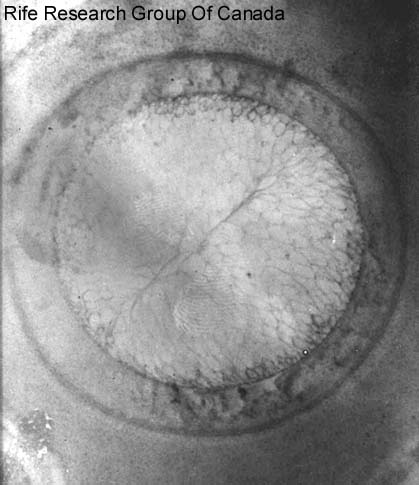

Ameba 5000x Histolitica

Typhoid Bacteria with Rife Stain

Enlarged to 300,000x

E. Coli with Rife Stain 6000x

Tuberculosis in rod Form

Strombilitis Intestinalis

T.B. Kidney - Rods in Cells, 2000x AgNO3 Stain

Tetanus